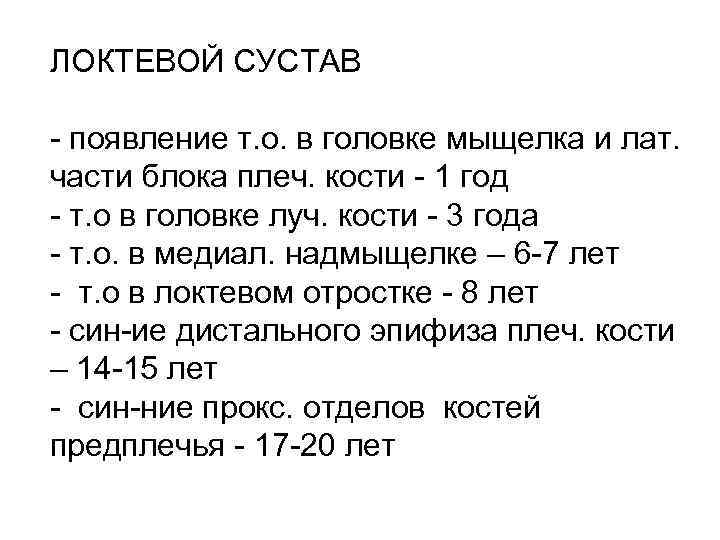

ЛОКТЕВОЙ СУСТАВ - появление т. о. в головке мыщелка и лат. части блока плеч. кости - 1 год - т. о в головке луч. кости - 3 года - т. о. в медиал. надмыщелке – 6 -7 лет - т. о в локтевом отростке - 8 лет - син-ие дистального эпифиза плеч. кости – 14 -15 лет - син-ние прокс. отделов костей предплечья - 17 -20 лет

ЛОКТЕВОЙ СУСТАВ - появление т. о. в головке мыщелка и лат. части блока плеч. кости - 1 год - т. о в головке луч. кости - 3 года - т. о. в медиал. надмыщелке – 6 -7 лет - т. о в локтевом отростке - 8 лет - син-ие дистального эпифиза плеч. кости – 14 -15 лет - син-ние прокс. отделов костей предплечья - 17 -20 лет